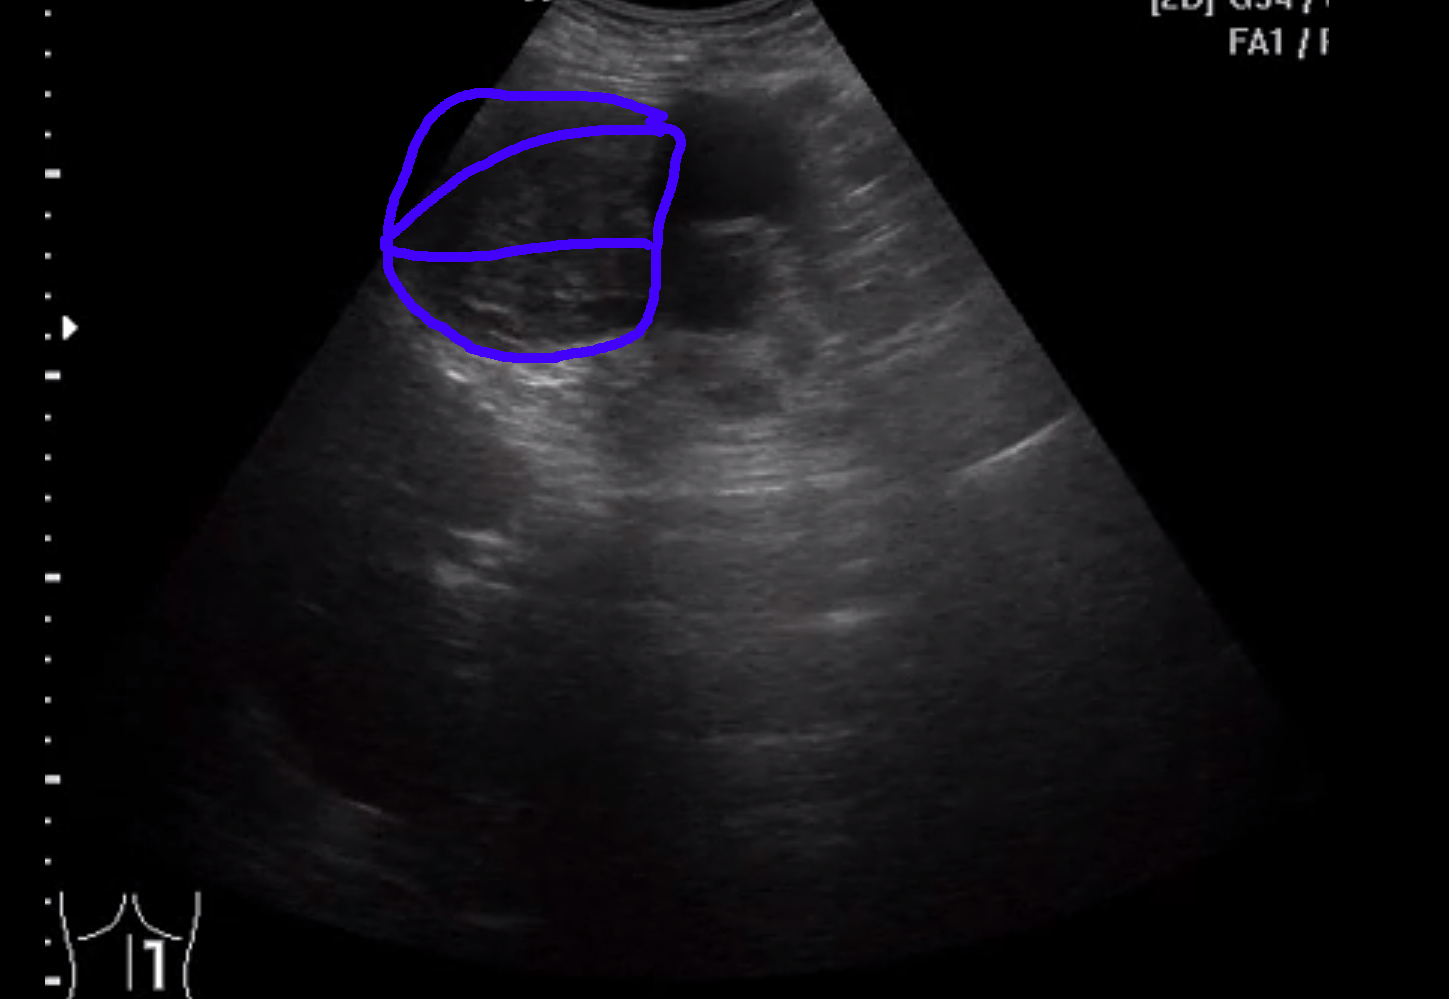

Вот здесь видно

Слева <-- видна опухоль (синий цвет в снэпшоте внизу), а справа -> почка со угадываемыми очертаниями.

Снимок экрана 2015-07-22 в 21.49.27.png